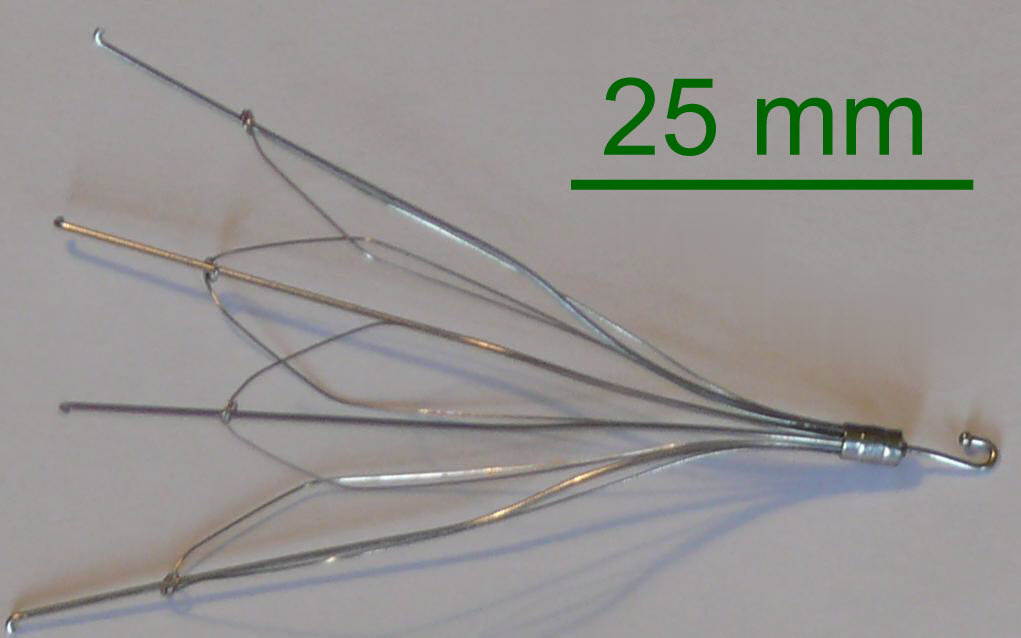

فیلتر ivc قلبی یا فیلتر ورید اجوف تحتانی (Inferior Vena Cava Filter یا IVC Filter) یک دستگاه پزشکی کوچک است که در ورید اجوف تحتانی (IVC) قرار میگیرد تا لختههای خون را قبل از رسیدن به ریهها گیر بیندازد و از آمبولی ریوی (PE) جلوگیری کند. این فیلترها عمدتاً برای بیمارانی استفاده میشوند که VTE (ترومبوآمبولی وریدی) دارند اما نمیتوانند از ضد انعقادها استفاده کنند، مانند موارد خونریزی فعال یا جراحیهای پرخطر.

فیلتر ivc قلبی به دستههای دائمی، قابل بازیابی (retrievable)، convertible و bioconvertible تقسیم میشوند. اکثر مدلها از مواد مانند Nitinol یا stainless steel ساخته شدهاند و شکل مخروطی یا cage-like دارند.

- Greenfield (Boston Scientific): مدل کلاسیک stainless steel یا titanium، معرفیشده در 1973، با پاتنسی بالا و مناسب برای IVC تا 28 mm.

- TrapEase (Cordis/Johnson & Johnson): شکل cage-like، دائمی.

مدلهای قابل بازیابی (retrievable): - Denali (BD/Bard): پیشرفته، با نرخ بازیابی بالا و کاهش tilt/migration.

- Günther Tulip و Celect/Celect Platinum (Cook Medical): محبوب، با anchoring legs، اما ریسک perforation.

- Option (Argon Medical): مشابه Denali، اما گاهی سختتر بازیابی.

- OPTEASE (Cordis): retrievable تا مدت محدود، cage-like.

مدلهای قدیمیتر Bard (با عوارض بیشتر، منجر به lawsuits): - Recovery, G2, G2 Express, Eclipse, Meridian.

مدلهای نوین: - Sentry (Boston Scientific): bioconvertible، خودکار بازشونده.

- VenaTech Convertible (Braun).

انتخاب مدل بر اساس قطر IVC، مدت نیاز و ریسک عوارض است. تا 2025، تمرکز بر مدلهای با نرخ بازیابی بالا مانند Denali و Celect Platinum است.